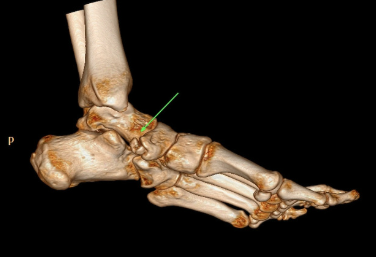

엑스레이 검사로 부주상골의 존재 유무와 크기를 확인하며, 평발 여부도 평가합니다.

MRI나 초음파 검사를 통해 주변 조직 염증과 후경골 건의 상태를 검사하여 중증도를 파악하고 다른 질환과 감별합니다.